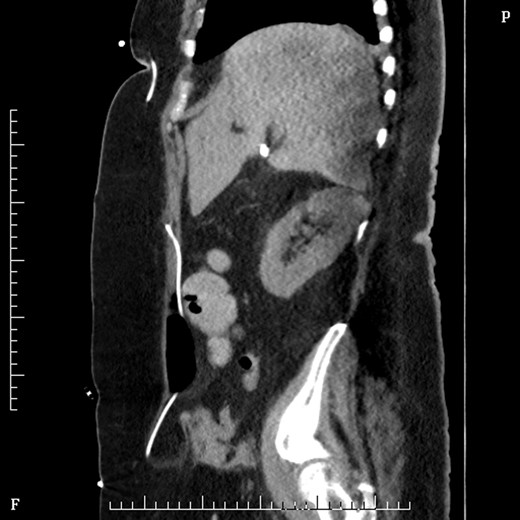

On Day 2 post VP shunt insertion, she was noted to be slow to recover and CT abdomen was performed. This demonstrated that the distal catheter tip was not in the pleural space but entered the abdomen and was redirected out along a tract into an umbilical hernia (Fig. 5). The following day she was taken back to theatre and the VP shunt was revised, and good visualization into the abdomen gave the impression that it was correctly in place. Repeat CT abdomen was performed to confirm placement and to our surprise the catheter had re-entered the same tract and travelled into the umbilical hernia (Fig. 6).

Sagittal figure CT abdomen, demonstrating catheter entering abdomen and re-exiting out the umbilical hernia.